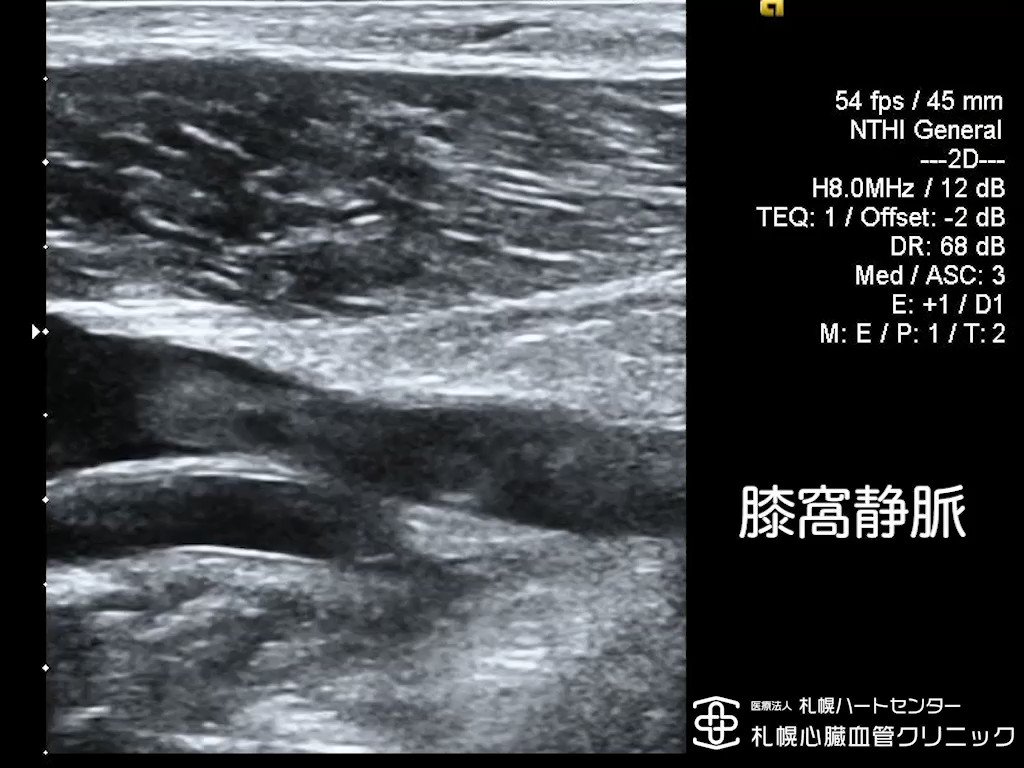

北海道心臓協会。

大動脈、腹部・下肢動脈エコーの攻略法動画ライブラリ。

下肢動静脈超音波検査。